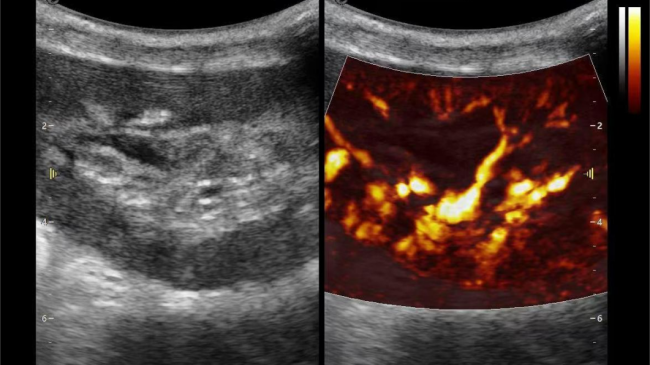

1) 基于OmniSound?平面波超快速平台,超声信号采集帧频提高了200倍(25000Hz)。

2) 可检测20-50μm级细小血管低速血流信号,能看清头发丝1/2粗细的微血管;

3) 通过血管指数(VI)定量评估局部血管密度,以定量化数据实时监测血流灌注情况,预判肾功能恢复情况;

超微视血流显像显示肾脏五级血管

超微视血流显像评估肾移植术后灌注情况